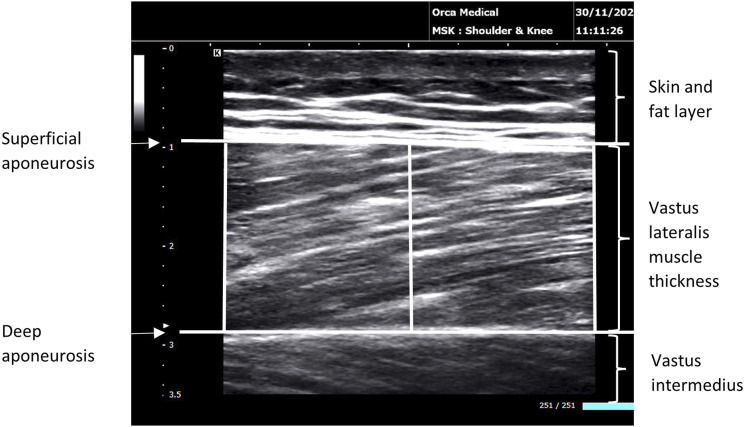

ObjectiveThe study aims to evaluate the between-day reliability of a proposed test battery for patients with claudication that can be used for monitoring the effectiveness of exercise interventions and other therapeutic strategies tailored to this patient population.MethodsTwenty-five men with claudication were recruited. The test battery consisted of the Vastus Lateralis muscle thickness (VL-MT), ankle-brachial pressure index (ABI), unilateral isometric knee extension maximal voluntary torque (MVT) and 6-minute walk test (6MWT). A single investigator conducted the tests for each patient on two separate testing sessions (T1 and T2) 5-7 days apart.ResultsGood to excellent reliability was observed for VL-MT (ICC = 0.95, 95% LOA = ±3.10 mm, SEM = 0.81 mm), ABI (ICC = 0.97, 95% LOA = ±0.10, SEM = 0.02), MVT (ICC = 0.97, 95% LOA = ±24.0 N·m, SEM = 6.31 N·m), 6MWT distance (ICC = 0.99, 95% LOA = ±39.6 m, SEM = 11.0 m), 6MWT time to claudication (ICC = 0.99, 95% LOA = ±30.8 s, SEM = 7.8 s), and 6MWT ratings of pain (ICC = 0.87, 95% LOA = ±2.4 CR-10+, SEM = 0.7 CR-10+ ). Analysis derived from reliability data indicates a change of 1.4 mm for VL-MT, 0.14 for ABI, 12 N·m for MVT, 25 m for 6MWT distance, 15 s for 6MWT time to claudication and 1 CR-10+ for 6MWT ratings of pain is required to be interpreted as the minimum 'likely' change (76% chance).ConclusionsThe test battery provides a reliable assessment of patients with claudication and can be widely used to evaluate the effects of exercise programmes and other therapeutic interventions. For the individual, changes in VL-MT, ABI, MVT, and 6MWT greater than the minimum likely change as a result of an exercise programme or an intervention are likely changes and less influenced by error associated with the test.